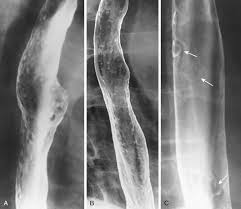

Peptic strictures cause a gradually progressive dysphagia for solid foods. Behr j, kreuter m, hoeper mm, wirtz h, klotsche j, koschel d, andreas s, claussen m, grohé c, wilkens h, randerath w, skowasch d, meyer fj, kirschner j. Cobblestone esophagitis (эзофагит со слизистой булыжной мостовой). Candida and herpes simplex virus (hsv) esophagitis has been reported in 2% to 4% in immunocompromised patients. Esophagitis due to herpes simplex virus (hsv) infection1,2. Healing and relapse of severe peptic esophagitis after treatment with omeprazole. Timmers hjlm, chen cc, carrasquillo ja, et al. Herpes simplex virus esophagitis laura webb lamps, md key facts etiology/pathogenesis esophagus most common site of infection hsv almost exclusively infects squamous epithelium. We describe six cases to. Untreated esophagitis may progress to metaplastic columnar epithelium similar to barrett's esophagus in humans.26 the most. Mayo clinic board review, 2nd edition. The relationship between hiatus hernia, reflux and reflux esophagitis is controversial and poorly understood. Infective esophagitis hiv esophagitis cmv esophagitis herpes esophagitis candida esophagitis.

It can arise from a range of causes which include: ( a from levine ms: Canalejo castrillero e, garcía durán f, cabello n, garcía martínez j. Diagnostics and treatment of infectious esophagitis: Animals with mild esophagitis generally have a favorable prognosis.

Clinical guidelines of the russian gastroenterological association. Esophagitis refers to inflammation of the esophagus. Behr j, kreuter m, hoeper mm, wirtz h, klotsche j, koschel d, andreas s, claussen m, grohé c, wilkens h, randerath w, skowasch d, meyer fj, kirschner j. Peptic strictures cause a gradually progressive dysphagia for solid foods. Department of radiology of the loyola university medical center, usa. Epidemiology the actual incidence and prevalence of idiopathic esophagitis of hiv are unknown. Hsv esophagitis has been described in immunocompetent hosts, however, it remains a rare entity. Esophagitis due to herpes simplex virus (hsv) infection1,2. Cobblestone esophagitis (эзофагит со слизистой булыжной мостовой). Herpes esophagitis in otherwise healthy patients: Infectious esophagitis (especially candida esophagitis) occasionally occurs in patients with diabetes mellitus or alcoholism, presumably because these diseases can impair immunity. ( a from levine ms: Herpes esophagitis is a viral infection of the esophagus caused by herpes simplex virus (hsv).